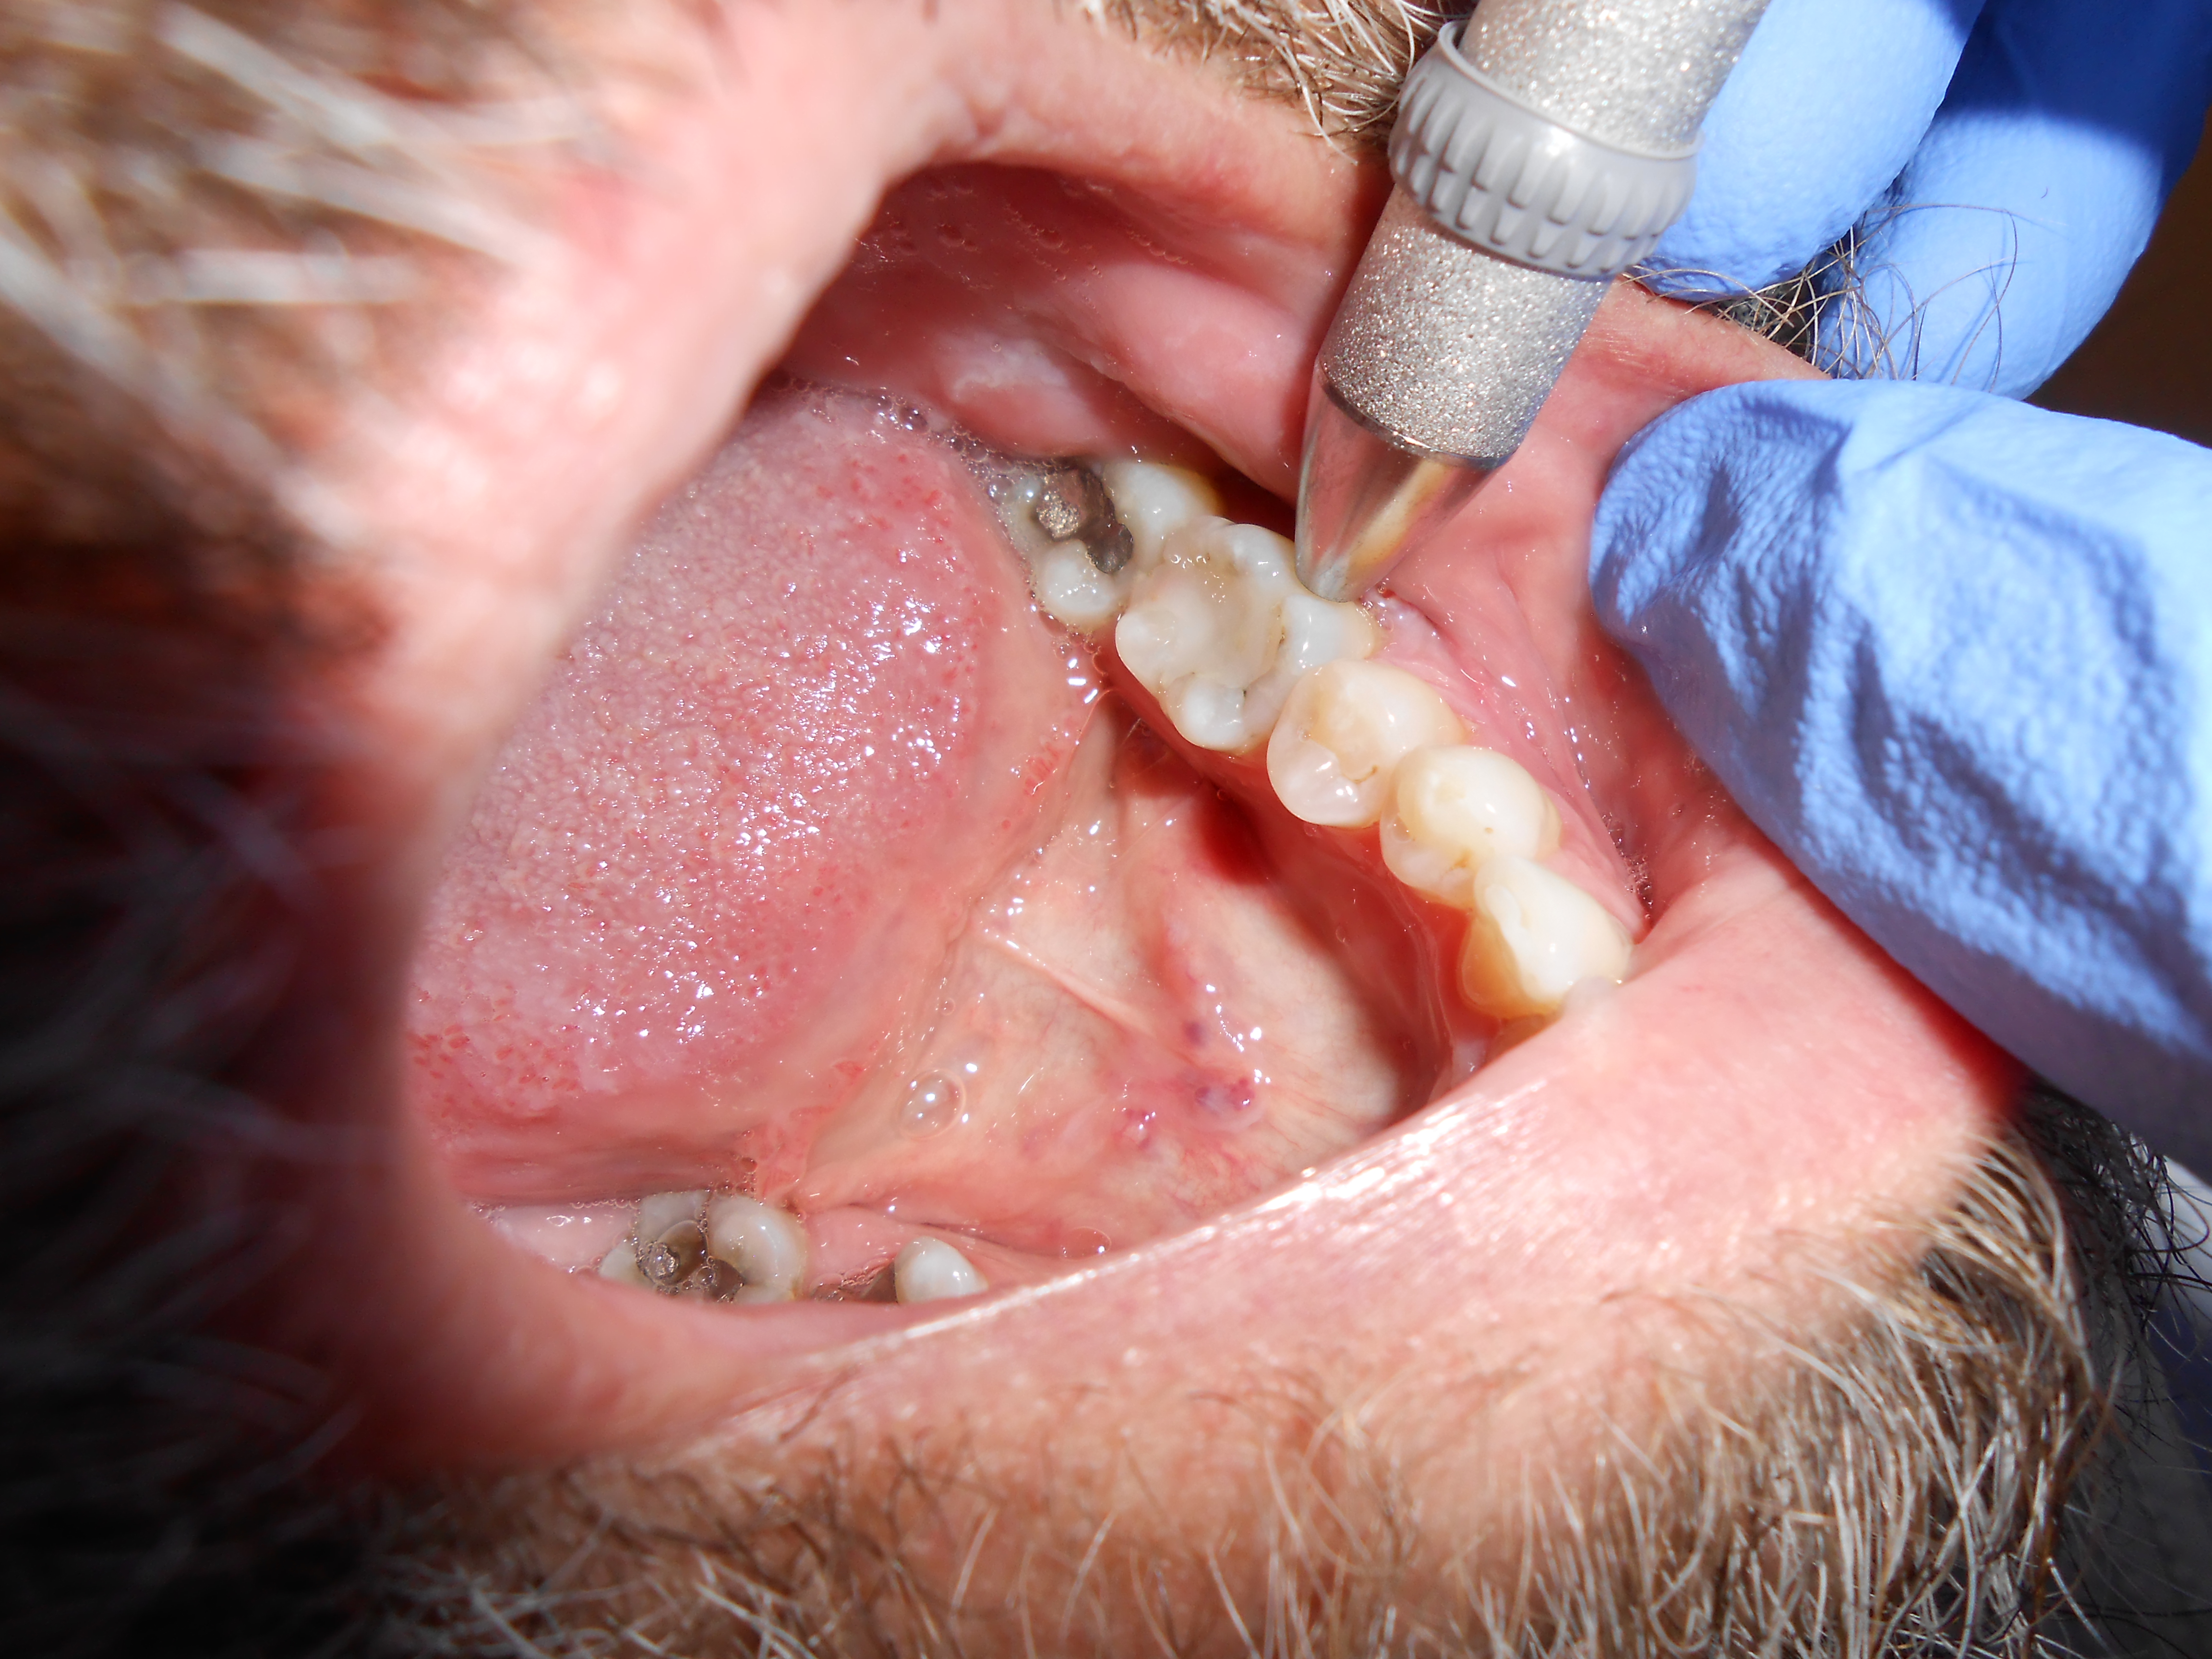

Fig 3. Determining a diagnosis with a radiograph only can lead the clinician to treat tooth No. 29 because of the distal decay. However, if the proper diagnostic tests are performed on tooth No. 29, it should reveal the pulp tested necrotic and it is tooth No. 30 that has a symptomatic irreversible pulpitis.

Figure 3

When a patient presents for restorative treatment and reports that a tooth is asymptomatic, a dentist may assume that the pulpal and periradicular diagnosis is within normal limits and hence may skip the above objective clinical tests, with the possible exception of taking a radiograph. However, using only a dental radiograph to determine the etiology of tooth pain and the pretreatment pulpal and periradicular status may lead to a pulpal and periradicular misdiagnosis (Figure 3). Therefore, a clinician must perform all five objective tests to obtain an accurate pretreatment pulpal and periradicular diagnosis.